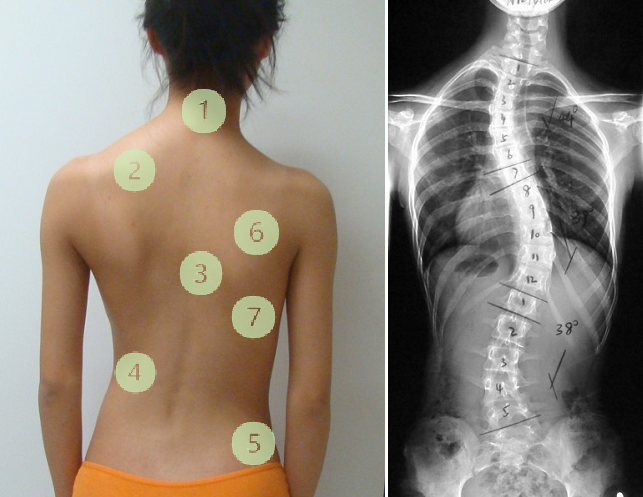

体态不对称是脊柱侧弯患者会出现的普遍现象,这种外观的不对称可以从正面、背面来观察,头部、肩膀、胸部、腰部、骨盆、背部都有可能因为侧弯出现左右两边不平衡的状态。

对应图示看几个方面:

①头部倾斜,会发现两边的耳朵高度不一样。

②高低肩,即左右两肩不等高,有较明显的一边高一边低的现象。

③身体偏斜,严重的身体明显偏向一边,头部不在身体的中线上。

④左右两边腰线不对称,一边的腰线比较明显,向内凹,但另一边的腰线很平。

⑤臀部歪一边,穿裤子时可以发现裤腰的位置明显不平衡,一边高一边低。

⑥两边肩胛骨不对称,一侧较突出。

⑦背部有明显的一边高一边低。

如果发现有以上不对称状况,哪怕只是其中一个部位有明显不对称,都要引起重视。